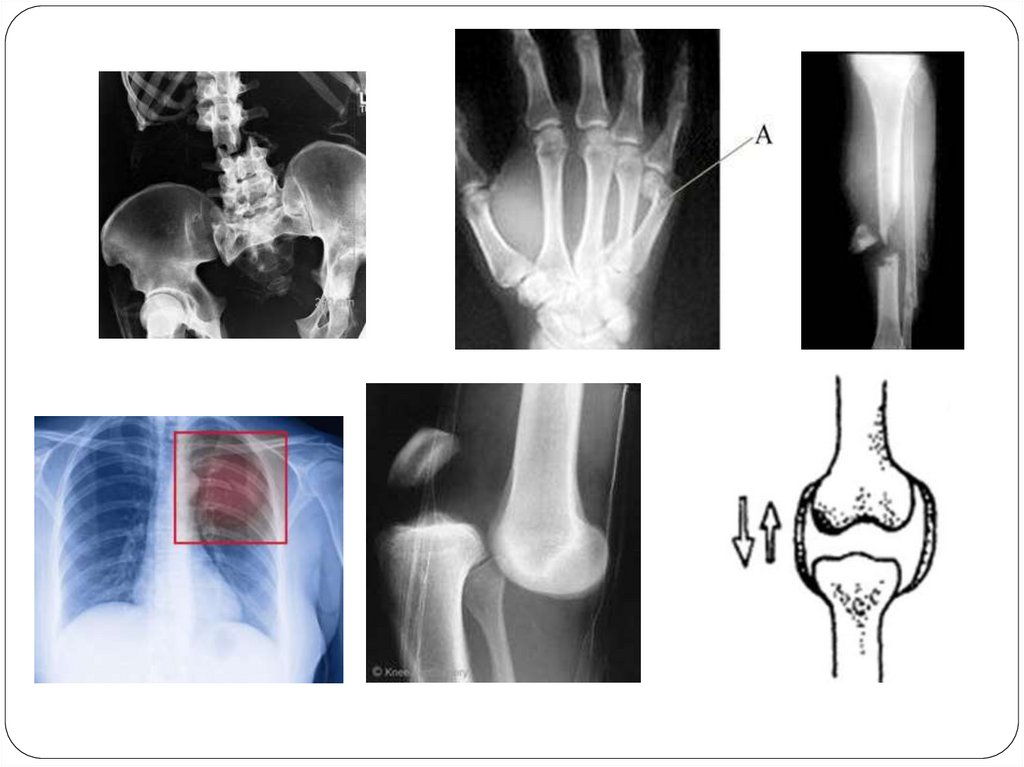

Первая помощь при травмах:

растяжении связок, вывихах

суставов, переломах костей

Урок биологии 8 класс

Тема

«Первая помощь

при повреждениях

опорно-двигательной системы»